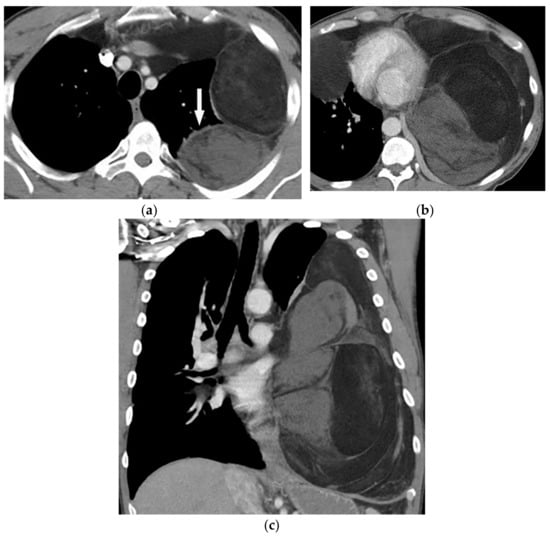

Figure 3.

An 18-year-old woman with vague chest pain. The axial plane CT in the bone window obtained at the level of four chambers shows large destructive soft tissue mass within the posteromedial aspect of the chest wall on the left side with internal ossification that has a “sunburst” appearance (arrow) (a,b). The coronal view also shows the same large destructive soft tissue mass with internal calcification (arrow), which is denser centrally (c).